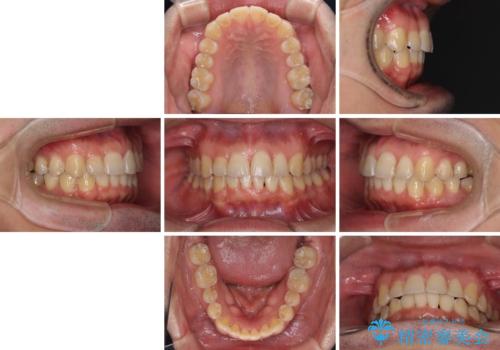

ディープバイトと叢生を解消 インビザライン矯正

- 前歯のデコボコを強い咬みしめを気にして来院された患者様です。

インビザラインを用いて、前歯の叢生を解消するとともに、ディープバイトを改善していくこととしました。

ディープバイトが改善されたことで、顎への負担が軽減され、更には上顎前歯の突出感も改善することができました。

矯正治療後には欠けてしまった修復物をセラミックインレーにて修復治療しました。